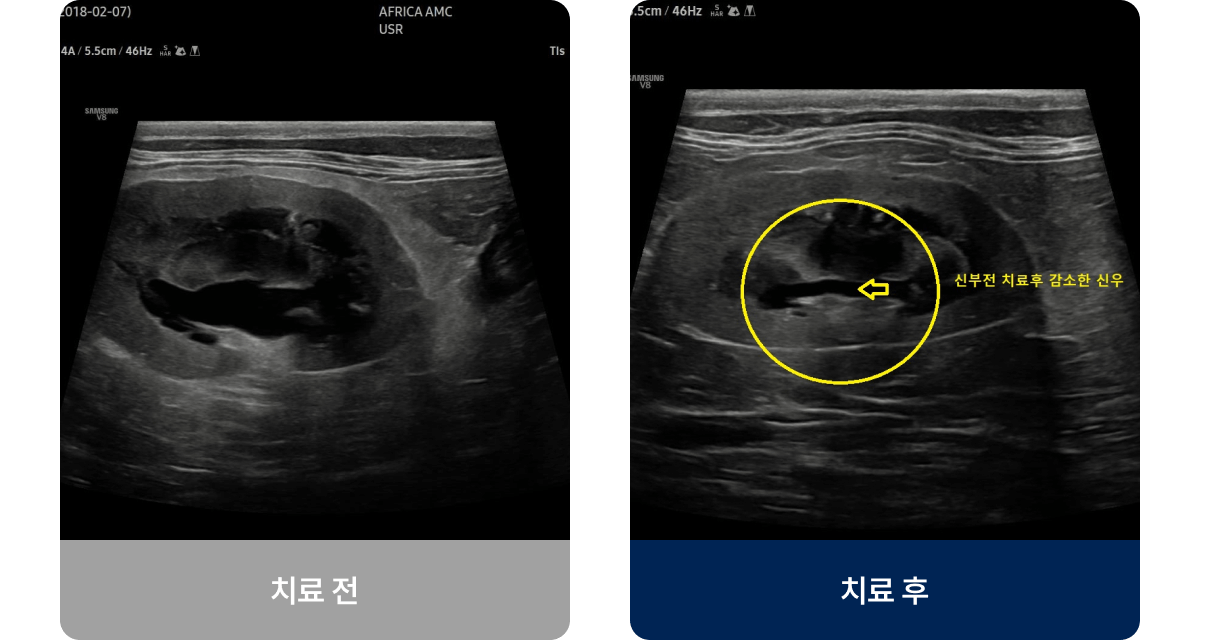

노화나 탈수, 고혈압, 유전적 요인 등으로 신장의 여과 기능이 서서히 저하되는 질환입니다. 주로 7세 이상 노령견이나 고양이에게 많이 발생하며, 물을 많이 마시고 소변량이 늘거나 식욕이 감소하는 증상을 보입니다. 진행되면 구토, 체중 감소, 입 냄새, 무기력 등 전신적인 증상으로 이어질 수 있습니다.

내과적 치료법(비수술적 치료)

손상된 신장을 되살리는 것은 어렵지만,

남은 기능을 최대한 유지하고 증상을 완화하는 치료입니다.